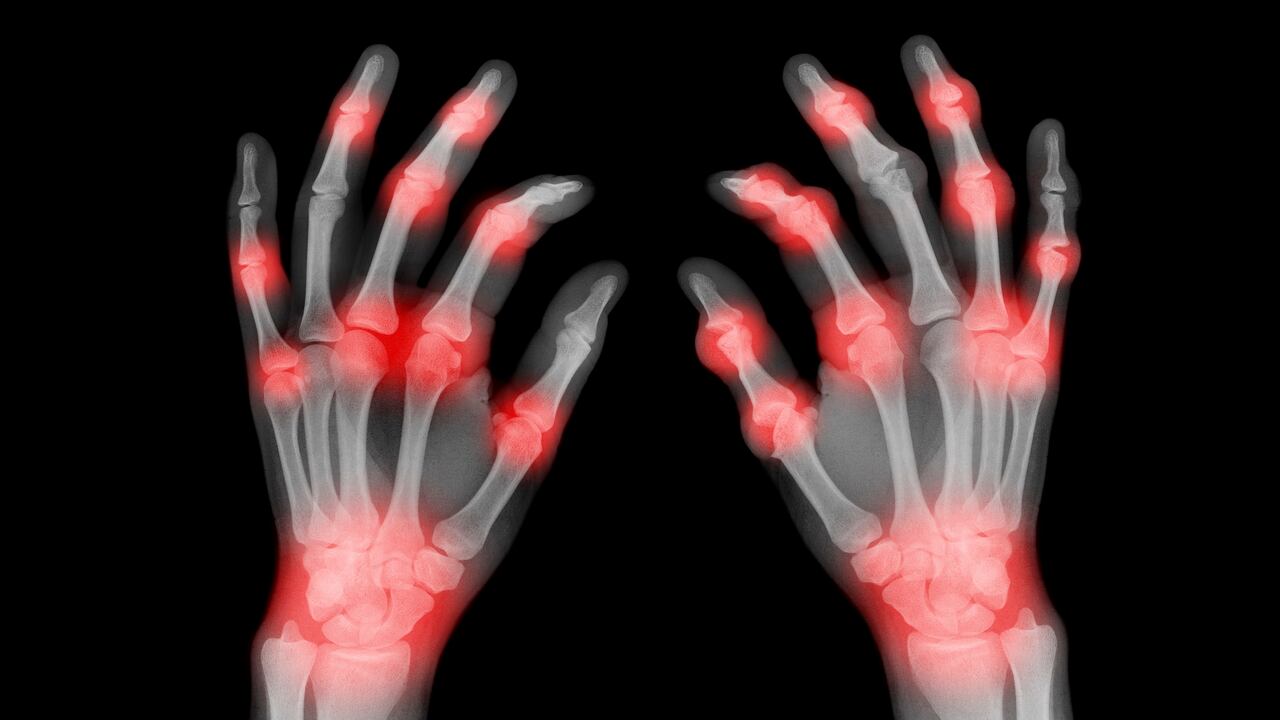

Igualmente, esta molestia a menudo es un signo de alerta de la artritis. Según Mayo Clinic, esta enfermedad consiste en la hinchazón y sensibilidad de una o más articulaciones, y se caracteriza por producir dolor y rigidez en las articulaciones.

Existen varias clases de artritis, sin embargo, las más comunes son la artrosis y la artritis reumatoide. Dependiendo de cuál de estas padezca la persona, la artritis se puede tratar de distintas maneras, con el ánimo de aliviar las molestias y propiciar una mejor calidad de vida a los pacientes, pero no tiene una cura definitiva.

En el caso de la artrosis, explica Mayo Clinic, se origina por un deterioro del cartílago de la articulación, que es el encargado de amortiguar los extremos de los huesos y permitir el movimiento de los mismos. Al dañarse esta capa, los huesos se muelen entre ellos, provocando dolor.

“En la artritis reumatoide, el sistema inmunitario del cuerpo ataca el revestimiento de la cápsula de las articulaciones, que consiste en una membrana dura que encierra todas las partes de las articulaciones. Este revestimiento (membrana sinovial) se inflama y se hincha. El proceso de la enfermedad puede finalmente destruir el cartílago y el hueso dentro de la articulación”, puntualiza Mayo Clinic.